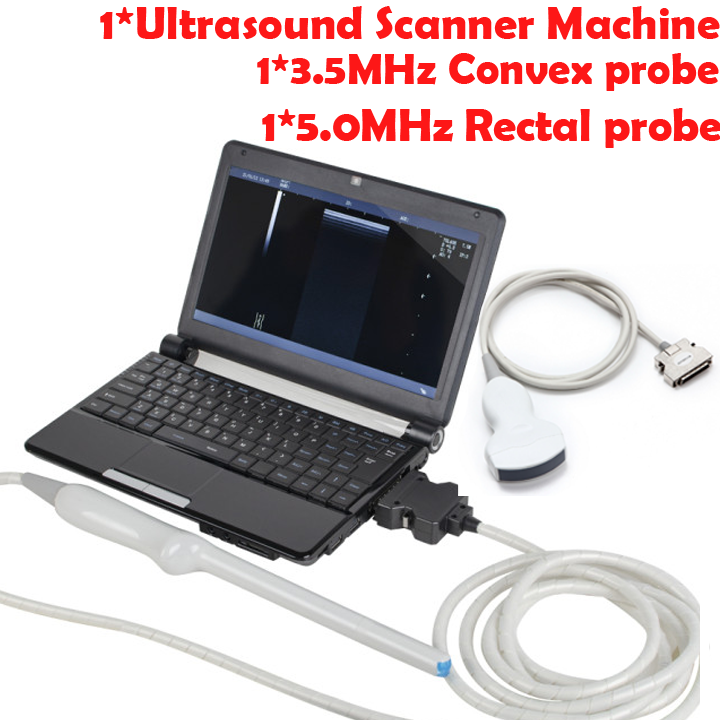

TFT LCD Digital Laptop Linear Array Ultrasound Scanner

But the benefits don’t just stop with the screen. This device is built for ease of use so medical practitioners can focus more on their patients and less on operating the machine. The laptop's compact design also means it’s highly portable, making it suitable for both in-clinic use and fieldwork. So, whether you’re conducting patient exams in a busy hospital or a rural clinic, this ultrasound scanner offers unmatched convenience and flexibility.

Versatility is another key advantage of this ultrasound scanner. It supports a variety of probes that allow for different types of examinations. In particular, the cavity probe included with this machine is useful for gynecological and obstetric purposes. Because this adds another layer of functionality to the device, healthcare providers can deliver comprehensive care using a single machine. With multiple probe options, you can seamlessly switch from one type of imaging to another without missing a beat.